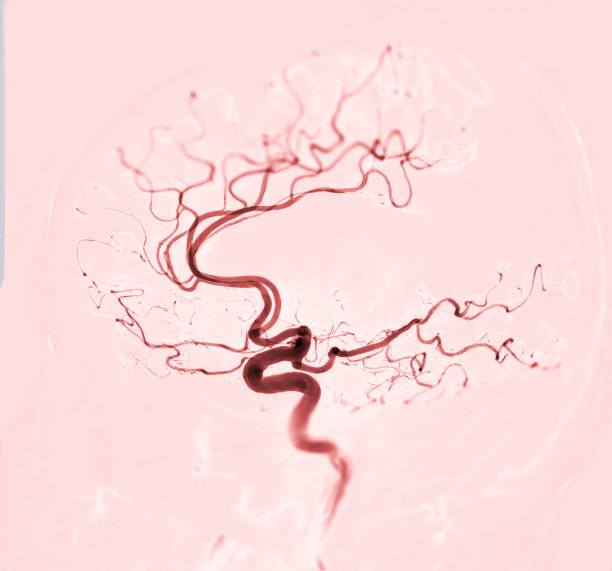

고혈압은 뇌출혈의 가장 큰 원인으로 볼 수 있는데 고혈압 환자라면 혈압이 갑작스럽게 상승하는데 이 때 산소와 영양소가 뇌로 들어가는 통로인 혈관에 변화를 일으키는데 혈관이 버티지 못하고 터지게 됩니다. 뇌동정맥의 기형에 의한 뇌출혈, 뇌동맥류 파열에 의하여 나타나며 잦은 흡연이나 다른 질병의 합병증으로 인해 발생할 수 있으며 뇌손상은 팔, 다리, 심하면 얼굴등 신체 일부분이 평생 마비시키며, 골든타임을 놓칠 경우 사망할 수도 있어 뇌출혈 전조증상에 대해 알고 있는 것이 좋습니다.